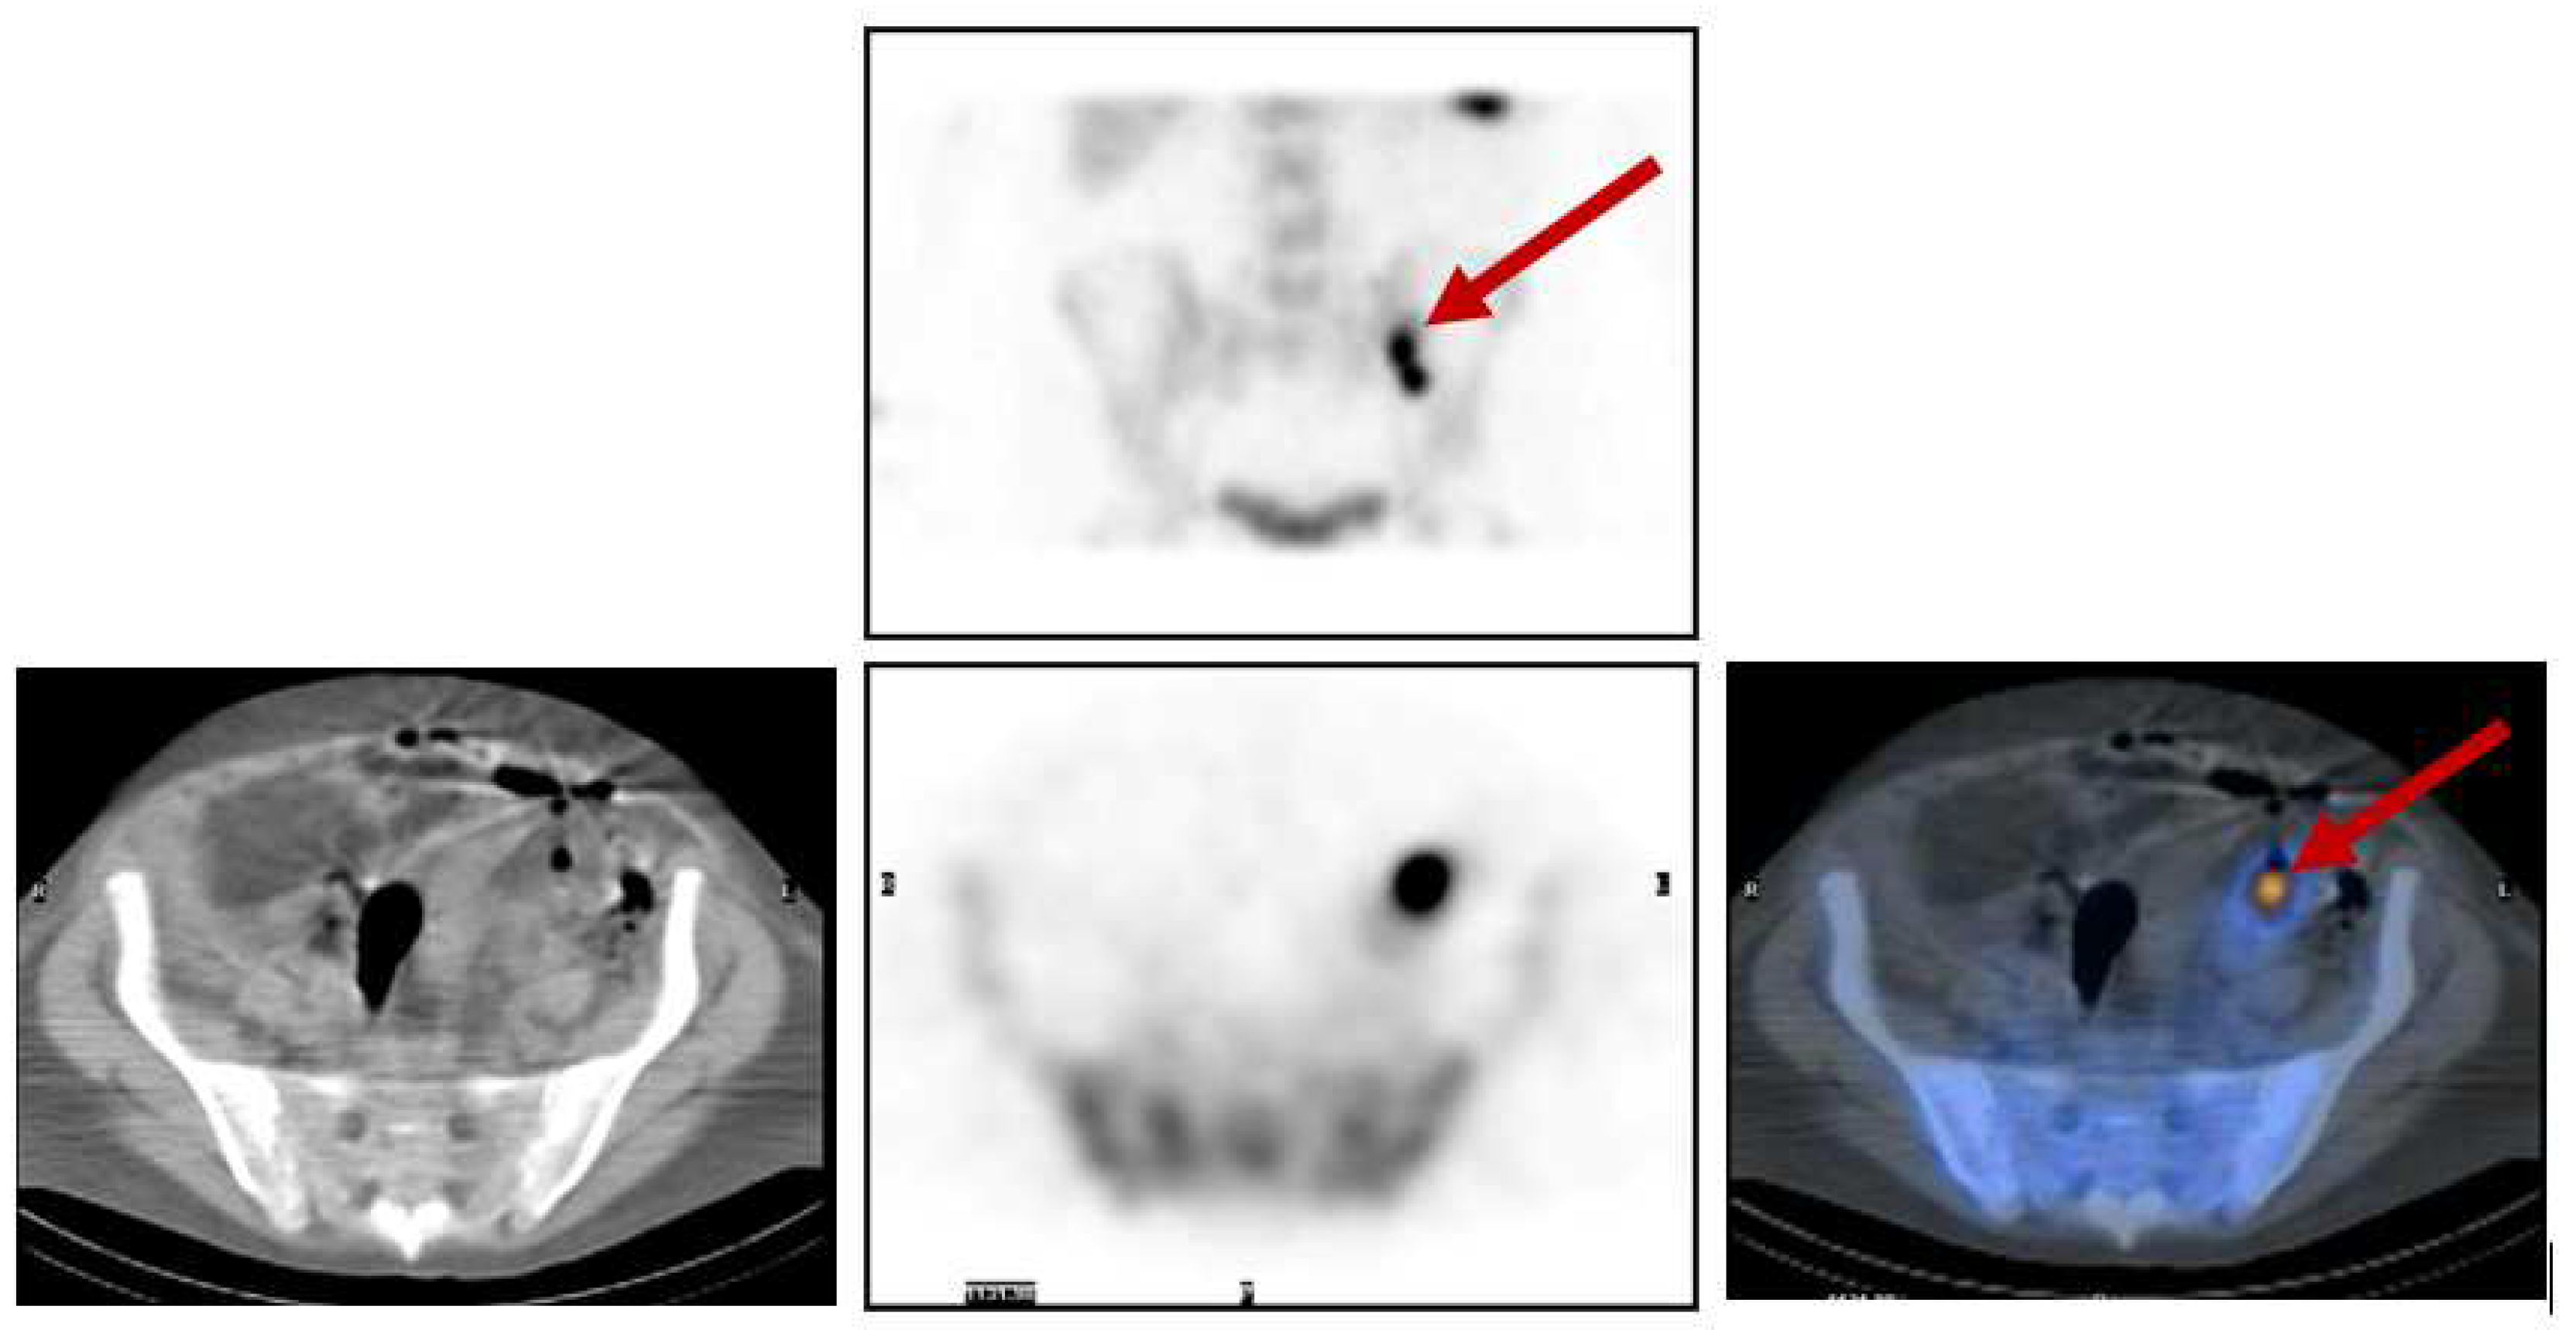

Figure 8 shows the clinical case of a 33-year-old male with fever of unknown origin, where all previous investigations had failed to detect the source of infection. Tc-99m white blood cells (WBC) whole-body scans and SPECT/CT detected and localized, respectively, an intra-abdominal abscess, as indicated by the arrows.

Figure 8.

Top row: Planar static image (anterior view). Bottom row: SPECT/CT axial images (CT slice—left; SPECT slice—middle; and fused images—right) that localise the abnormal uptake to an intra-abdominal abscess in the peritoneum.